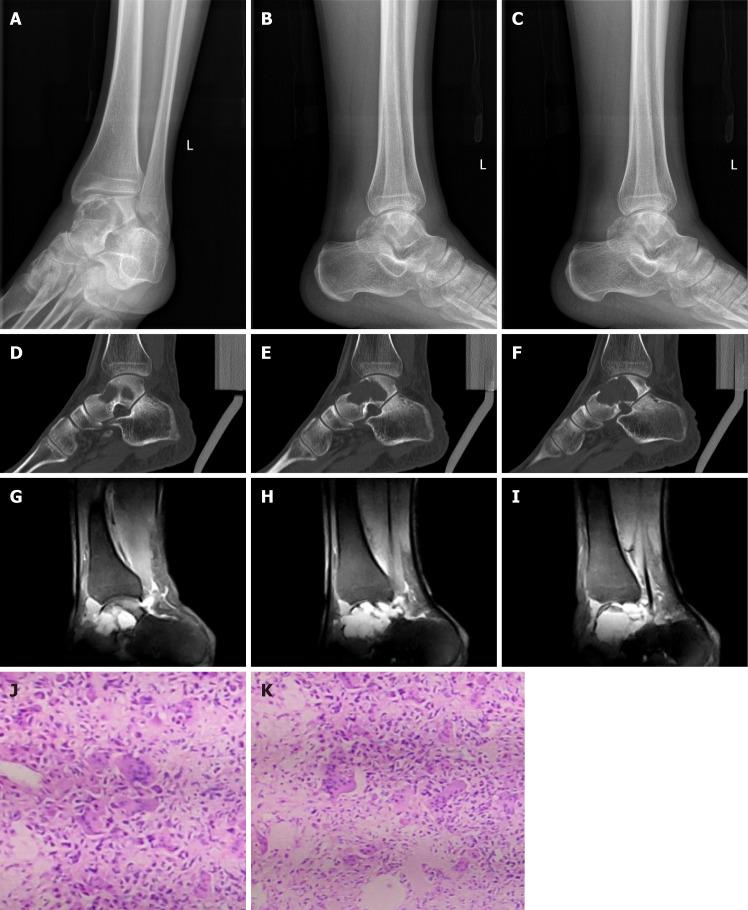

具有生物功能的三维打印距骨假体治疗距骨巨细胞瘤:1例报告并文献复习

Three-dimensional printed talar prosthesis with biological function for giant cell tumor of the talus: A case report and review of the literature.

We report a rare case of GCT of the talus in one patient who underwent a new reconstructive surgery technique using a three-dimensional (3D) printing talar prosthesis. The prosthesis shape was designed by tomographic image processing and segmentation using technology to match the intact side by mirror symmetry with 3D post-processing technologies. The patient recovered nearly full range of motion of the ankle after 6 mo. The visual analogue scale and American Orthopaedic Foot and Ankle Society scores were 1 and 89 points, respectively.

我们报告了1例距骨骨巨细胞瘤的罕见病例,该患者接受了一种使用三维(3D)打印距骨假体的新型重建手术技术。假体形状通过断层图像处理和分割技术进行设计,利用3D后处理技术通过镜像对称与完整侧匹配。6个月后患者踝关节恢复了几乎全范围的活动。视觉模拟评分和美国矫形足踝协会评分分别为1分和89分。